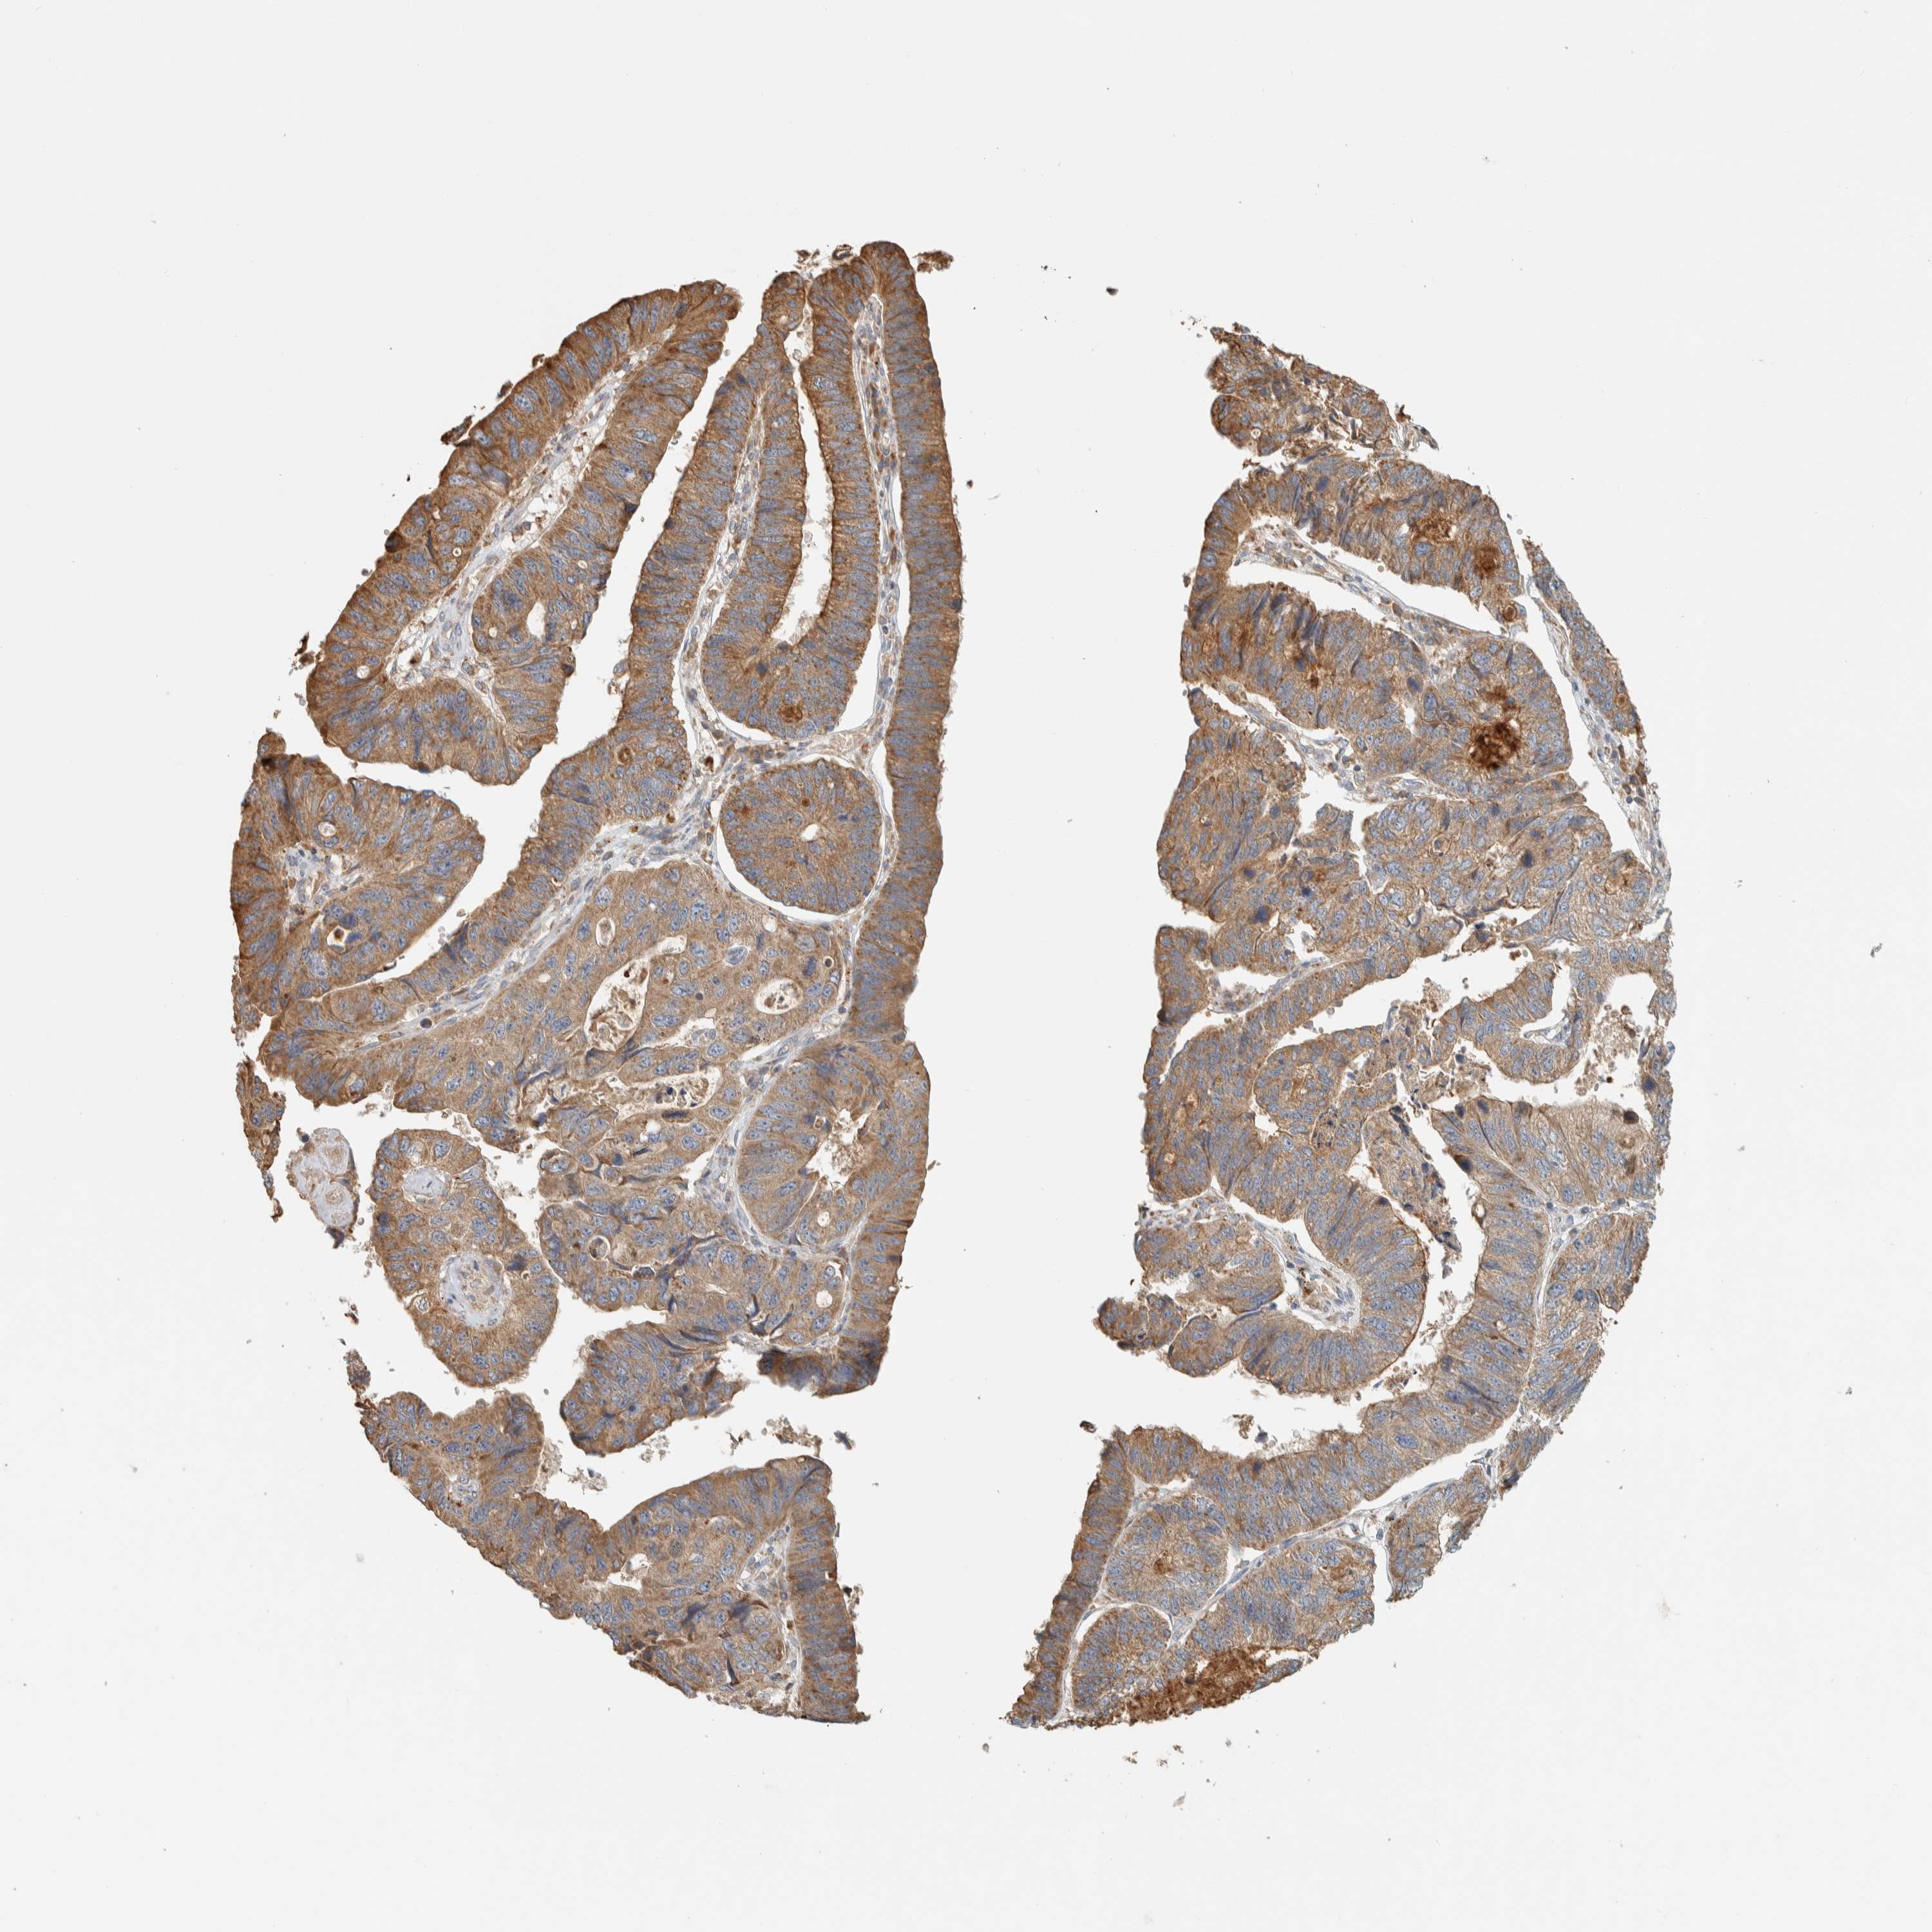

STOMACH CANCER - Protein expressioni

A mouse-over function shows sample information and annotation data. Click on an image to view it in a full screen mode. Samples can be filtered based on level of antibody staining by selecting one or several of the following categories: high, medium, low and not detected. The assay and annotation is described here.

Note that samples used for immunohistochemistry by the Human Protein Atlas do not correspond to samples in the TCGA dataset.

Antibody stainingi

Antibody staining in the annotated cell types in the current human tissue is reported as not detected, low, medium, or high, based on conventional immunohistochemistry profiling in selected tissues. This score is based on the combination of the staining intensity and fraction of stained cells.

Each image is clickable and will lead to virtual microscopy that enables deeper exploration of all samples and also displays staining intensity scores, fraction scores and subcellular localization as well as patient and tissue information for each sample.

Antibody HPA023904

Antibody HPA024010

Antibody HPA025960

Antibody CAB017037

Staining

High

Medium

Low

Not detected

Intensity

Strong

Moderate

Weak

Negative

Quantity

>75%

75%-25%

<25%

None

Location

Nuclear

Cytoplasmic/membranous

Cytoplasmic/membranous,nuclear

Adenocarcinoma, NOS